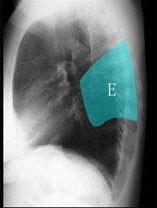

问题 在图所示正常胸部X线影像图像上,该英文字母所代表的肺段为 ( )

选项 A、后基底段 B、背段 C、前基底段 D、外基底段 E、内基底段

答案 B